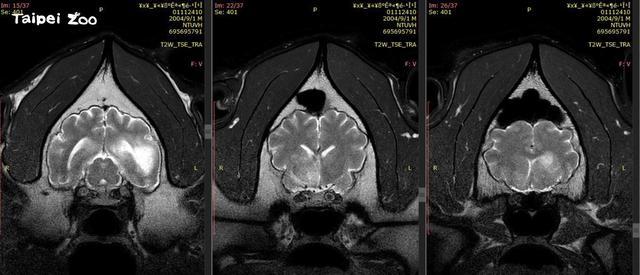

“团团”8月下旬发生癫痫症状,经核磁共振检查,发现其左右大脑半球均有局部液化病变坏死。

台北市动物园26日公布“团团”第二次核磁共振检查结果,称其病灶区域明显扩大,病程进展快速,脑部恶性肿瘤的机率大幅提高,但由于未能进行侵入性的切片(病理活检)检查,仍无法百分之百确认。

10月26日,台北市动物园公布了“团团”第2次核磁共振检查的结果。园方称,在联合各方专家诊断影像后,判断“团团”脑部病变除既有的病灶外,区域明显扩大,且出现肿块效应;病程进展快速,推测脑部恶性肿瘤的机率大幅提高。然而由于未能进行侵入性切片检查,仍无法百分之百确认。